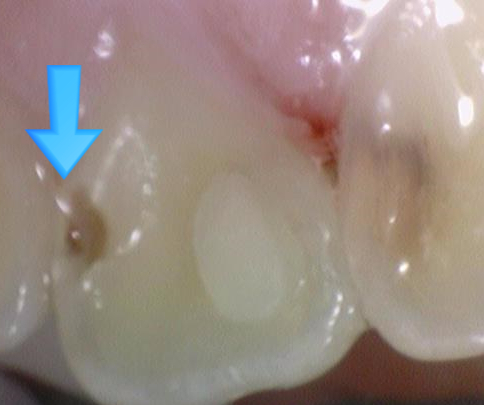

앞니사이 충치치료 레진치료

충치 3군데

입천장쪽에서 보면 충치 세 군데가 보입니다.

화살표 세 개중 맨 왼쪽 화살표가 가리키는 쪽은 충치가 명확하게 보이지 않지만

아주좋은 [!] 전문가의 눈으로 보면 충치가 비쳐보인다는 것을 알 수 있습니다.(대칭되는 반대쪽과 비교)

왼쪽 화살표 충치는 엑스레이로 다시 한번 명확하게 확인 하였습니다.